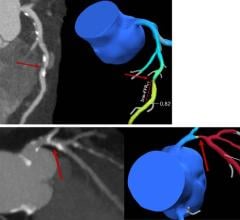

December 6, 2012 — Giving clinicians a more complete picture while improving safety during interventional procedures, Toshiba America Medical Systems Inc. introduces Spot Fluoroscopy for its Infinix-i angiography systems. Enabling quicker diagnoses and lower dose, clinicians can observe a target region of anatomy using Spot Fluoro’s live fluoroscopy while viewing the last image hold (LIH) surrounding area.

“Spot Fluoroscopy is like having an adjustable spot light over the reference LIH image, helping to reduce dose exposure and allowing the clinician to view the critical region of interest and the surrounding area at the same time,” said Stephen Bumb, director, X-ray Vascular Business Unit, Toshiba. “This unique type of unconventional collimation streamlines interventional procedures and reduces radiation exposure to both clinicians and patients, making exams safer for everyone involved.”